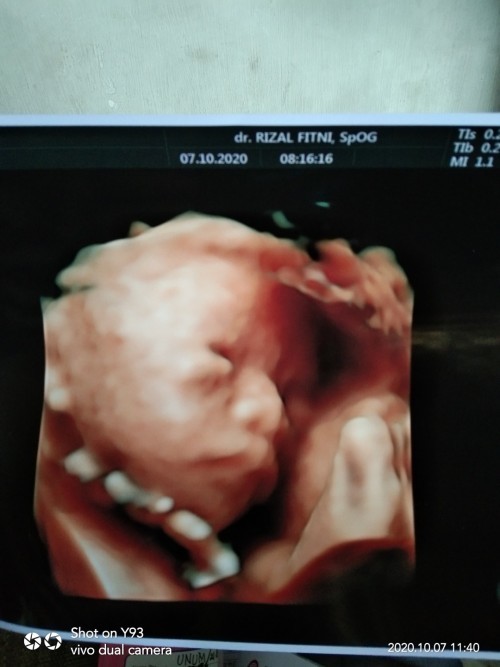

Pas usg di usia 26w, insya'allah jk cewek🤗